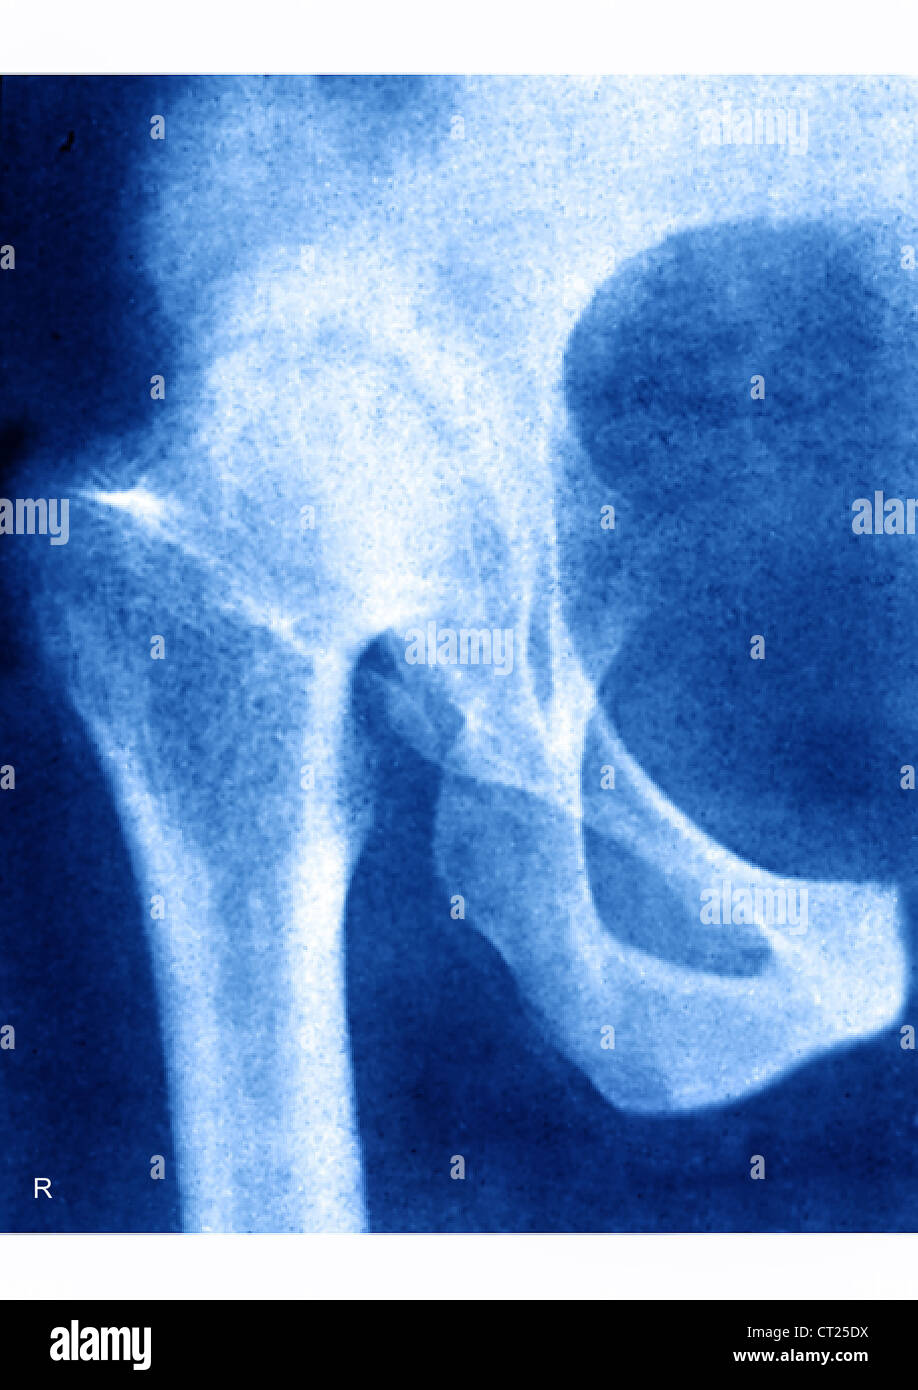

Hip X Ray With Osteoarthritis . A standard hip protocol includes an anteroposterior view. The scoring hip osteoarthritis with mri system evaluates eight mri features, including cartilage damage, subchondral bone marrow lesions, subchondral cysts, labral pathology, joint effusion, loose). Radiography is relatively inexpensive and is widely available. Different grading schemes are described for plain radiographs of the hip: Not much can be done for osteoarthritis of the hip. Radiography is the first line of imaging for hip pain and suspected oa. While it is not “curable”, it. Occasionally, a magnetic resonance imaging (mri) scan or a.

A standard hip protocol includes an anteroposterior view. While it is not “curable”, it. Different grading schemes are described for plain radiographs of the hip: Not much can be done for osteoarthritis of the hip. Radiography is relatively inexpensive and is widely available. Occasionally, a magnetic resonance imaging (mri) scan or a. The scoring hip osteoarthritis with mri system evaluates eight mri features, including cartilage damage, subchondral bone marrow lesions, subchondral cysts, labral pathology, joint effusion, loose). Radiography is the first line of imaging for hip pain and suspected oa.

Hip X Ray With Osteoarthritis The scoring hip osteoarthritis with mri system evaluates eight mri features, including cartilage damage, subchondral bone marrow lesions, subchondral cysts, labral pathology, joint effusion, loose). While it is not “curable”, it. Not much can be done for osteoarthritis of the hip. The scoring hip osteoarthritis with mri system evaluates eight mri features, including cartilage damage, subchondral bone marrow lesions, subchondral cysts, labral pathology, joint effusion, loose). Radiography is the first line of imaging for hip pain and suspected oa. Radiography is relatively inexpensive and is widely available. Different grading schemes are described for plain radiographs of the hip: A standard hip protocol includes an anteroposterior view. Occasionally, a magnetic resonance imaging (mri) scan or a.